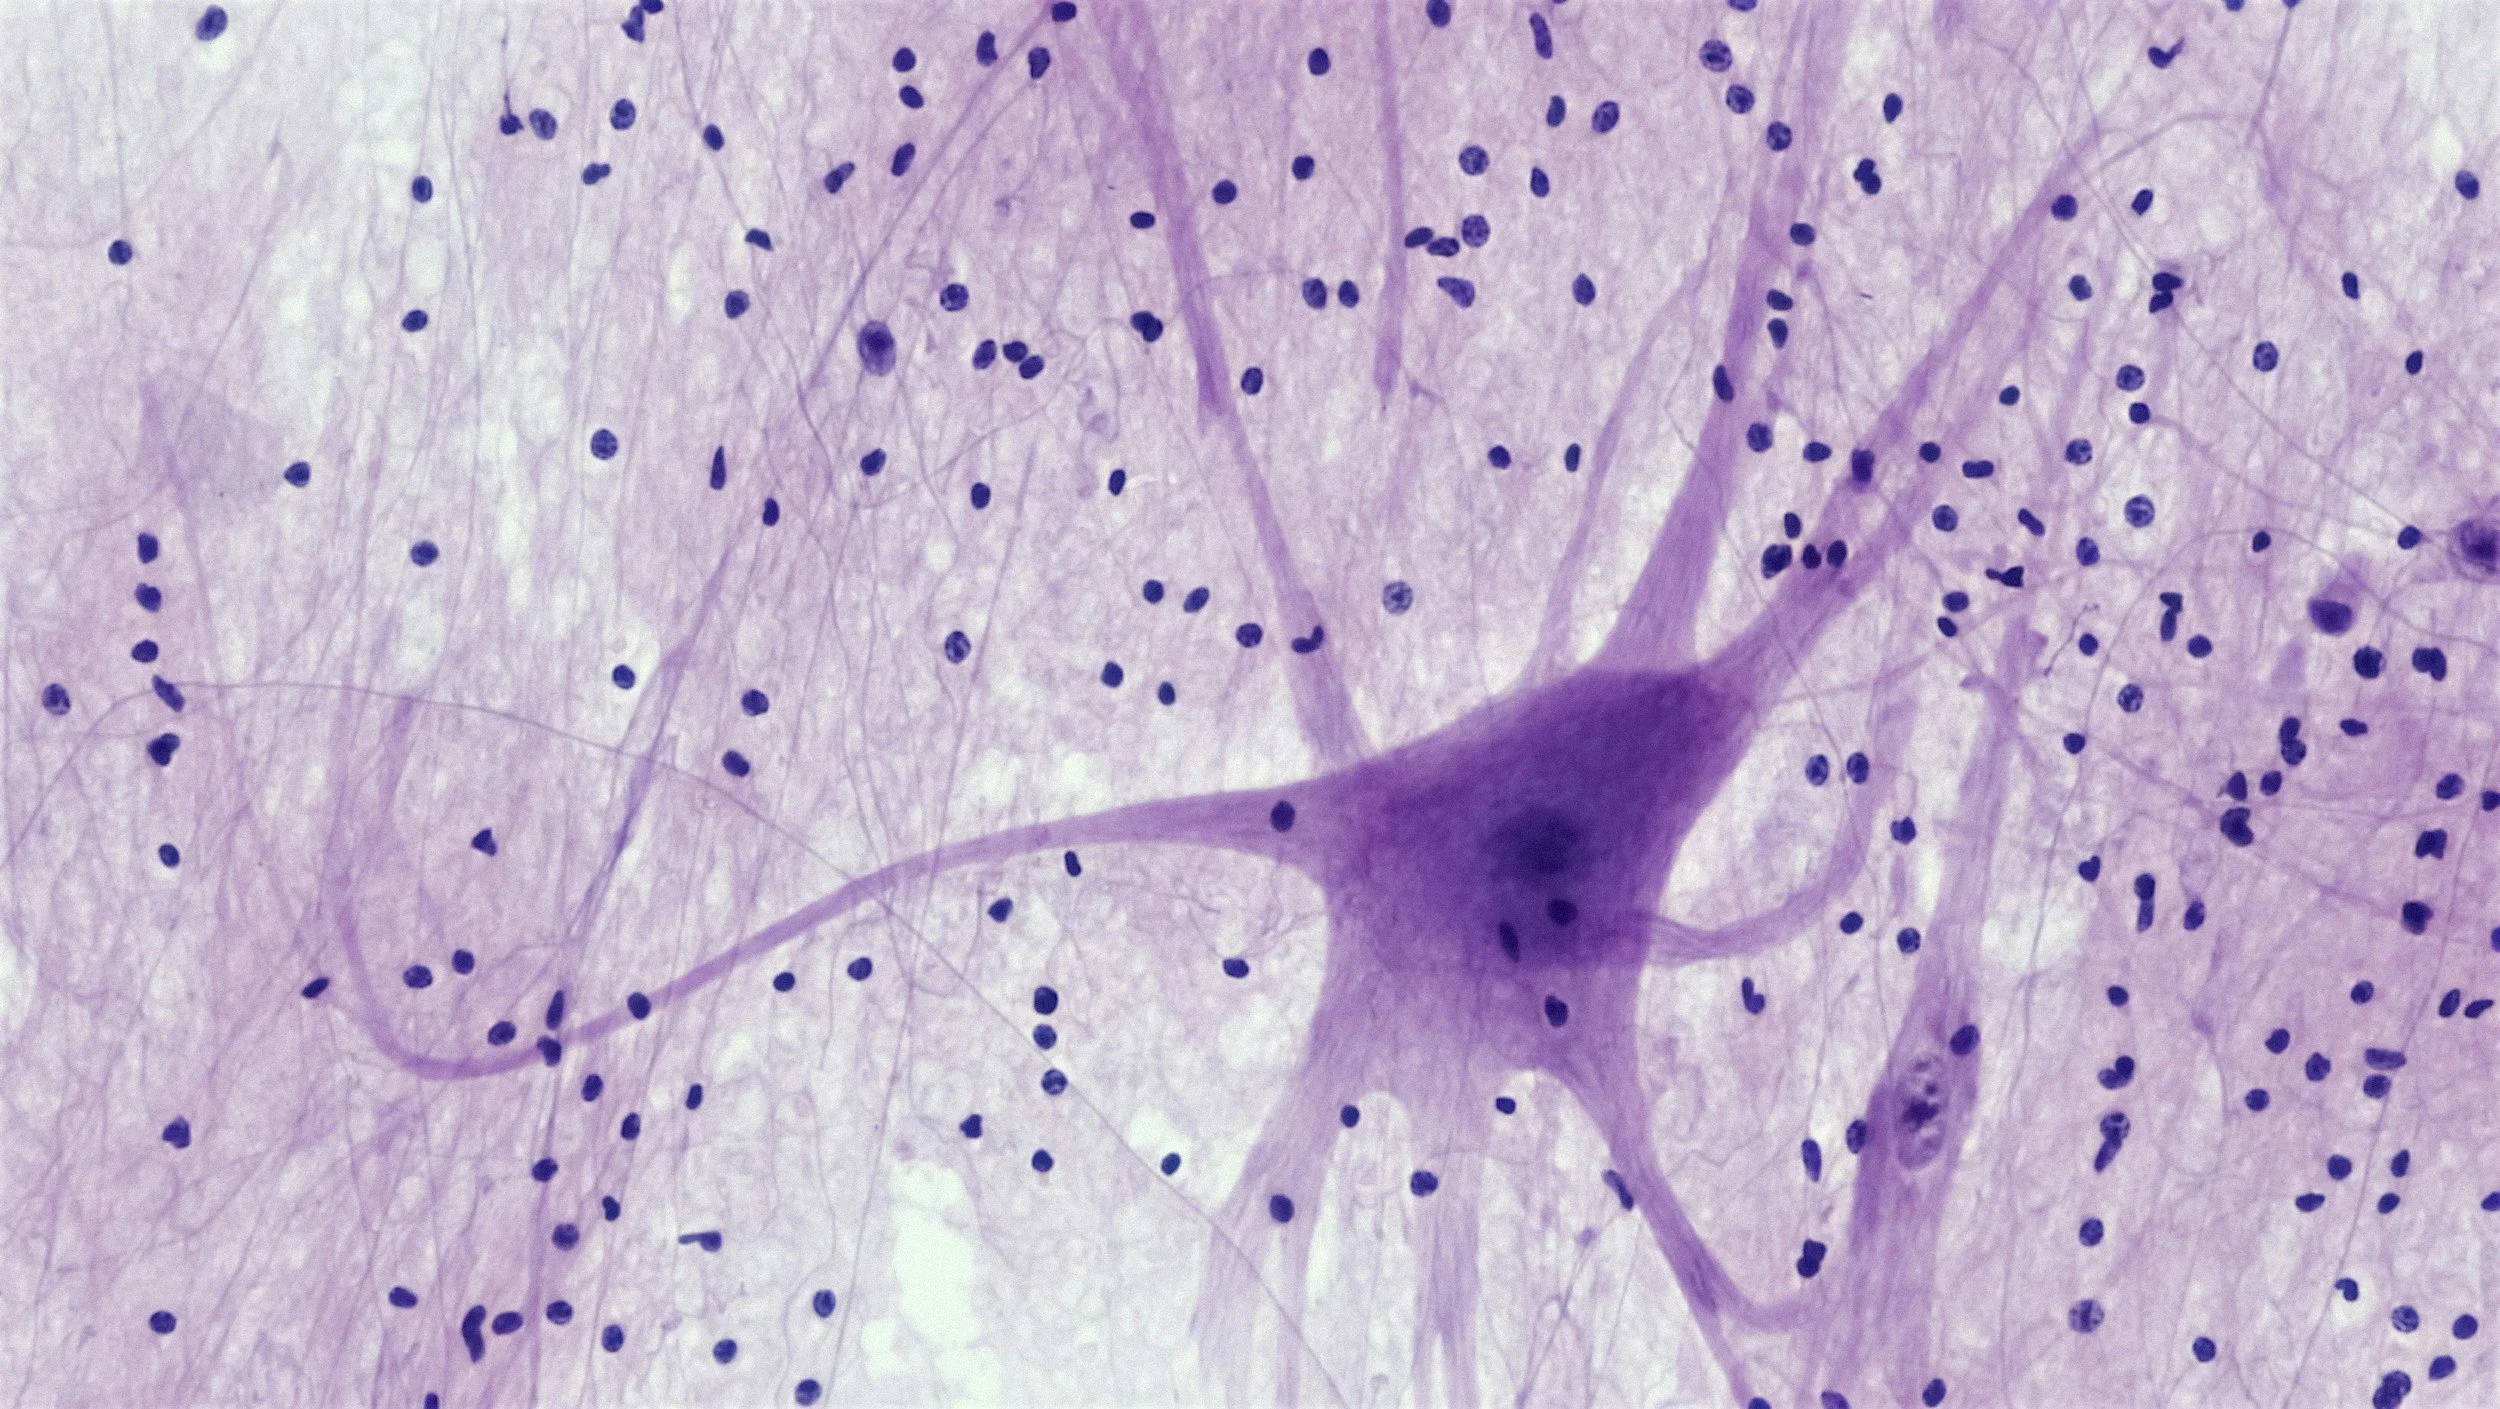

The Glioblastoma Research Organization’s vision is to advance global awareness of this aggressive and fast-growing brain cancer and to raise funds to find a cure. GBMRO partners with world-renowned cancer centers across the U.S. and Europe to support the research development of treatments and innovative therapies for Glioblastoma.